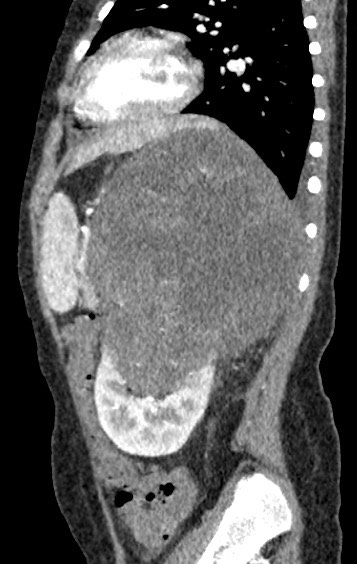

1384. Пациенту 5 лет с жалобами на увеличение живота и кровь в моче выполнена компьютерная томография, патологическим процессом, соответствующим клинико-рентгенологической картине, считают